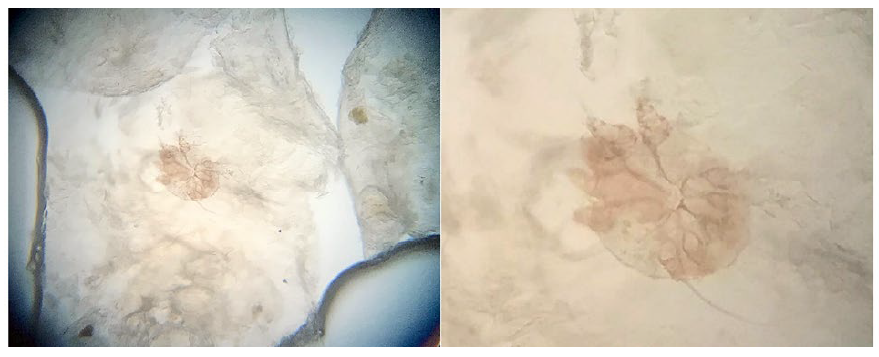

Como investigação complementar, foram realizadas biópsias cutâneas e análise microscópica de raspado de pele. O exame microscópico direto evidenciou numerosos ovos e parasitas Sarcoptes scabiei (Fig. 4). O exame anatomopatológico demonstrou hiperplasia epidérmica de padrão psoriasiforme, associada à ortoceratose e infiltrado perivascular composto por eosinófilos, evidenciando-se ácaro Sarcoptes scabiei na camada córnea (Fig. 5).

Figura 5 a) Hiperplasia epidérmica com padrão psoriasiforme (H&E, 4x). b) Infiltrado perivascular em derme com presença de eosinófilos (H&E, 10x). c e d) Hiperplasia psoriasiforme evidenciando ácaro Sarcoptes scabiei em camada córnea ortoceratótica (H&E, 4x; H&E, 10x).